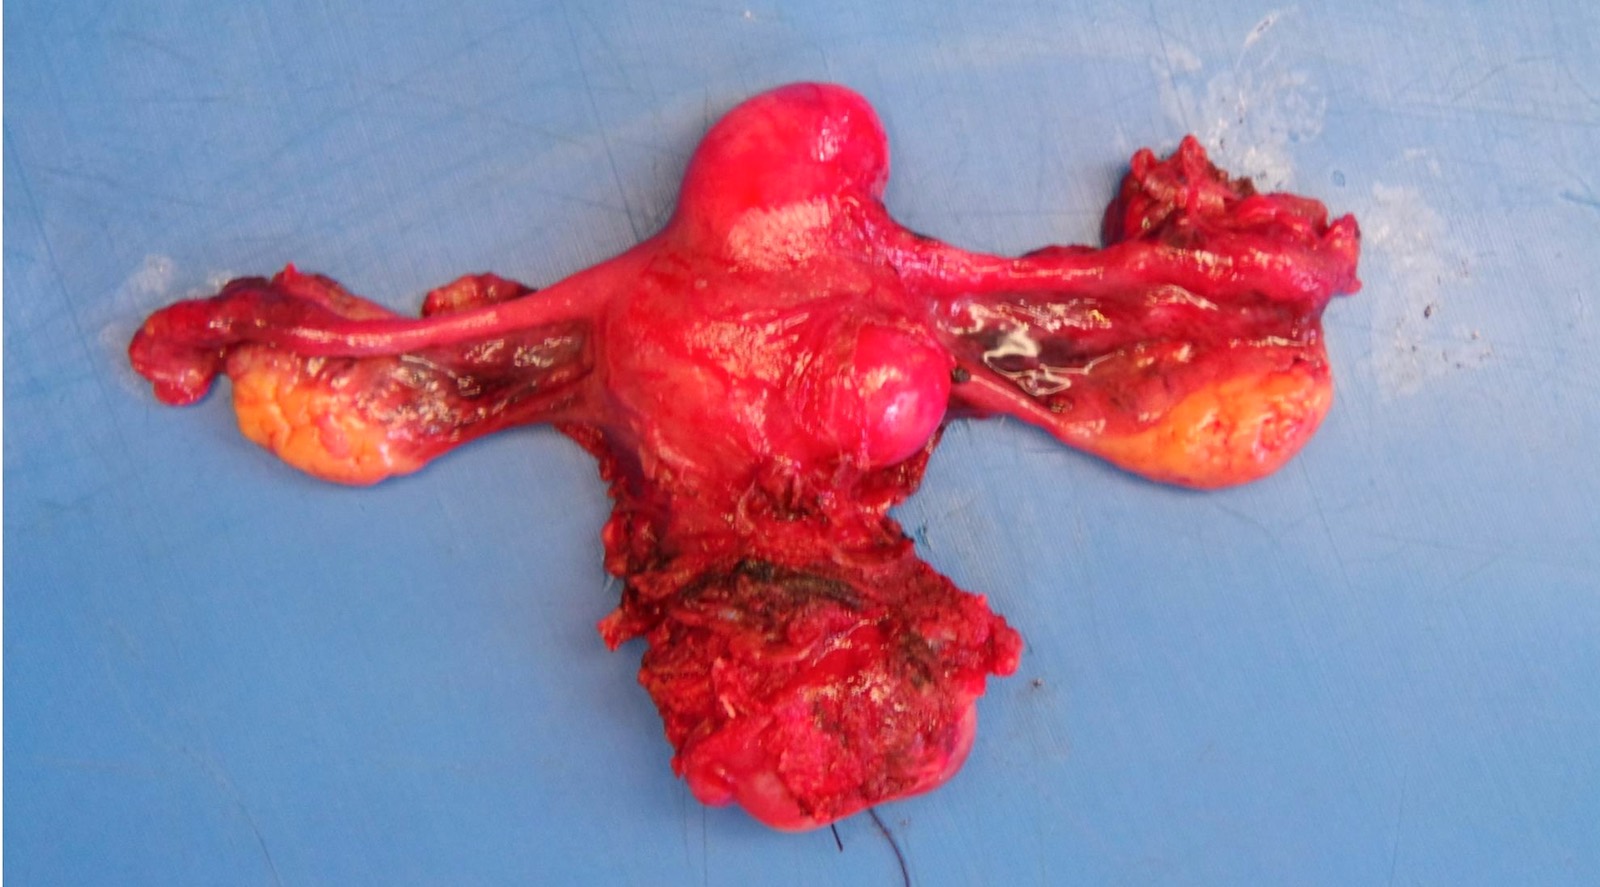

Gross description

- Location in the uterus: intramural, submucosal and subserosal

- Often multiple

- Typically well circumscribed but nonencapsulated

- On cut surface: white or tan-white, whorled, firm, bulging

- Hemorrhage and infarction can be present in large tumors

- Calcifications can be present

- Apoplectic change (foci of hemorrhage) associated with progesterone therapy

Gross images